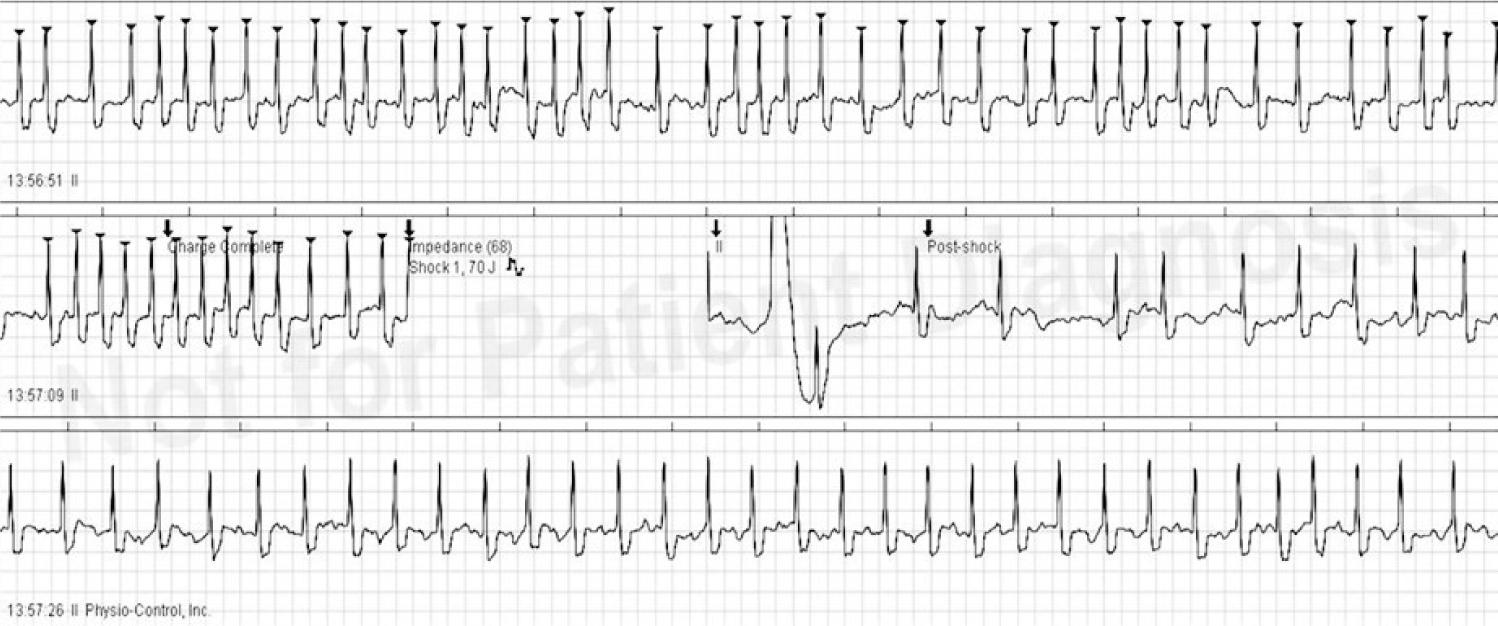

Fourteen privately-owned dogs admitted to the Cardiology Unit of the Department of Internal Medicine and Clinic of Horses, Dogs, and Cats of the Faculty of Veterinary Medicine, Wroclaw University of Environmental and Life Sciences, Poland, were enrolled into the study. They were dogs which had undergone complete physical, echo- and electrocardiographic examinations and been diagnosed with lone atrial fibrillation and none to minimal left atrial enlargement (LA/Ao <1.7). The dogs were mostly males (10/14), of mean age 5.92 ±1.47 years, weighing from 30 to 84 kg, and of various breeds, including five German Shepherds, three Central Asian Shepherd Dogs, one Giant Schnauzer, one Irish Wolfhound, one Polish Tatra Sheepdog, one Rhodesian Ridgeback, one Newfoundland, and one St. Bernard. The dogs were premedicated with dexmedetomidine (4 μg/kg) and midazolam (0.2 mg/kg) administered intramuscularly. After placing an intravenous catheter, general anaesthesia was induced with propofol (1 mg/kg) and fentanyl (2–5 μg/kg). Electrical cardioversion was performed using biphasic shock with energy of 70–360 J (Lifepak 12, Medtronic, USA) (Fig. 1). Recovery from the procedure was uneventful.

Successful electrical cardioversion of atrial fibrillation using biphasic shock with energy of 70J